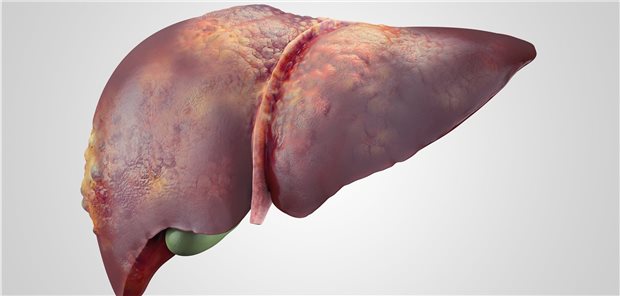

Leberkrebs wird bei jüngeren Menschen seltener, bei älteren häufiger diagnostiziert. Dies liegt auch an der sinkenden Bedeutung von Hepatitis und dem zunehmenden Einfluss eines ungesunden Lebensstils.